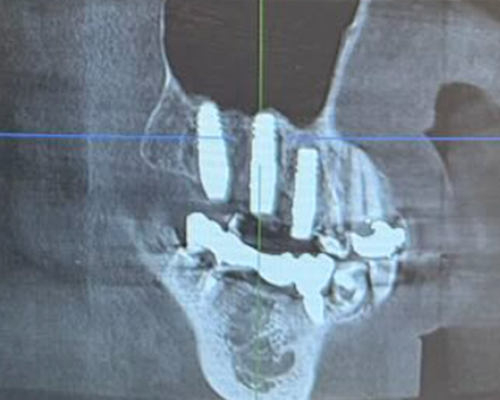

米国の技術×専属技工士×精密機器のフル活用で「短期治療」を実現!

米国の先端治療を安価で

年間1,000症例以上の 「世界レベル」オペ実施